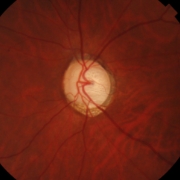

- 緑内障専門医が3名在籍。手術を含め的確な診断治療にあたります。

当院には3台の自動視野計がありますので、即日の検査が可能です。

緑内障に対する選択的繊維柱帯レーザー形成術を導入し、1年間に47眼に施行しました。4眼は無効、4眼は目薬を減らすことができ、36眼は3mmHg以上の眼圧の低下をみることができました。

副作用はほとんどありません。点眼薬で悩んでいらっしゃる方、ご相談ください。